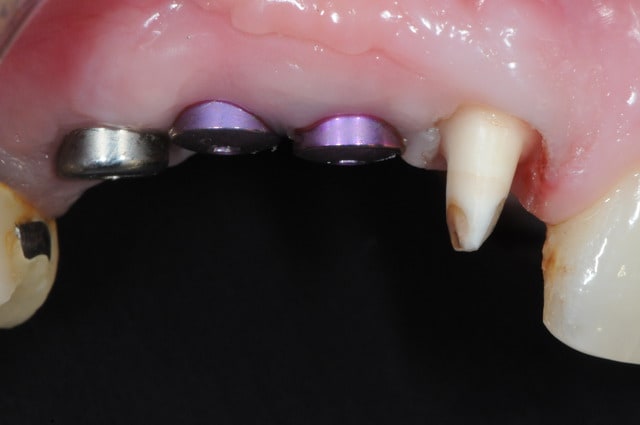

pose implants

cicatrisation gingivale

mise à jour et aménagement tissulaire type Palacci

piliers

couronnes...

bein pp il pose du victory....donc par déduction c'est un triple disk....;-)